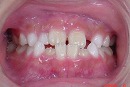

初診時 終了時

もし、初診時の様なかみ合わせで成長をつづけた場合を想像してみましょう。

将来の歯並びはどの様な状態となっている事でしょうか…?

早期に治療を開始することによって、

良好な歯並び、かみ合わせを維持しやすくなります。